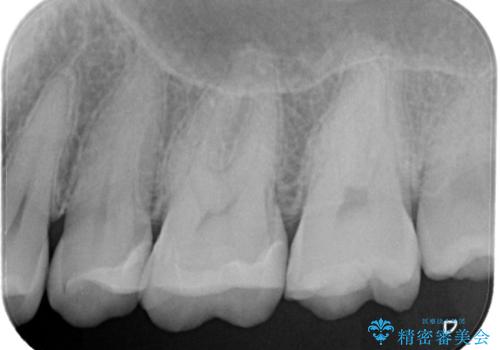

【セラミックインレー】定期検診で見つかった虫歯。

- 歯と歯の間で見つかりづらい虫歯でしたが、顕微鏡で確認し患者様に説明することで理解していただき、セラミックインレーにて修復治療を行いました。

以前にプラスチックの材料で修復した箇所が虫歯として見つかることはよくあります。